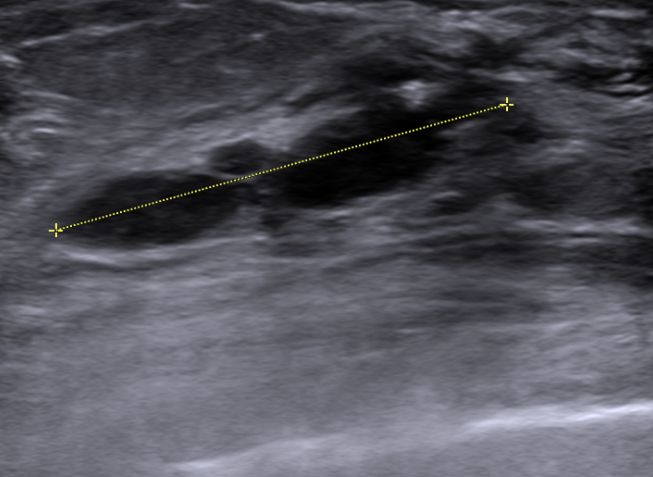

| Mammographie | 76-jährige Patientin mit multiplen Metastasen in Wirbelsäule und Leber. Zunächst kein Tastbefund der Brust. Dann suspekter Tastbefund rechts oben außen paramamillär. Mammographie zunächst o.B. befundet. Stanzbiopsie rechts oben außen: lobuläres Karzinom. | |||||||||